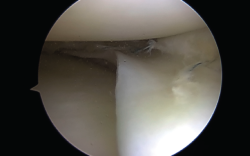

Figura 1. Rotura meniscal en asa de cubo.

El tratamiento artroscópico de las lesiones meniscales está indicado en aquellas lesiones que produzcan bloqueo articular, pacientes sintomáticos que no mejoren con tratamiento conservador o aquellos en quienes se vea afectado su nivel deportivo o laboral (Figuras 1 y 2).